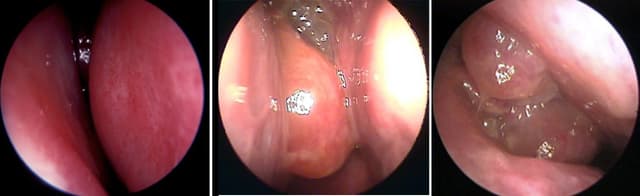

Viêm mũi họng xuất tiết là hiện tượng có dịch nhày đặc chảy từ khoang mũi và họng. Chúng có thể là triệu chứng bình thường khi niêm mạc mũi họng bị viêm. Đây là bệnh không đáng lo ngại vì có thể điều trị dứt điểm tuy nhiên nếu không được điều trị kịp […]